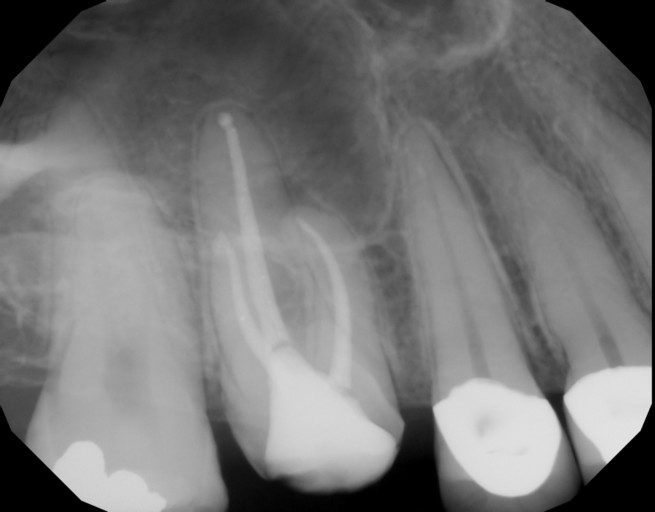

I had a RC (upper central incisor) done in the early 80s and have recently (last 15 years) experienced pain when eating/drinking hot liquids. I avoided them and the symptoms largely vanished. However, more recently (last 2 years), I have pain on palpation extending upwards into the opening of my nose and the tooth feels less secure. I am wondering if I need a RC retreatment or an apico. Can you help with the rough diagnosis and tell me what you think I should be doing at this time? Thanks in advance.